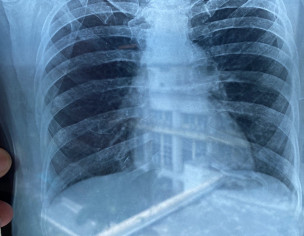

Attach Photo here: